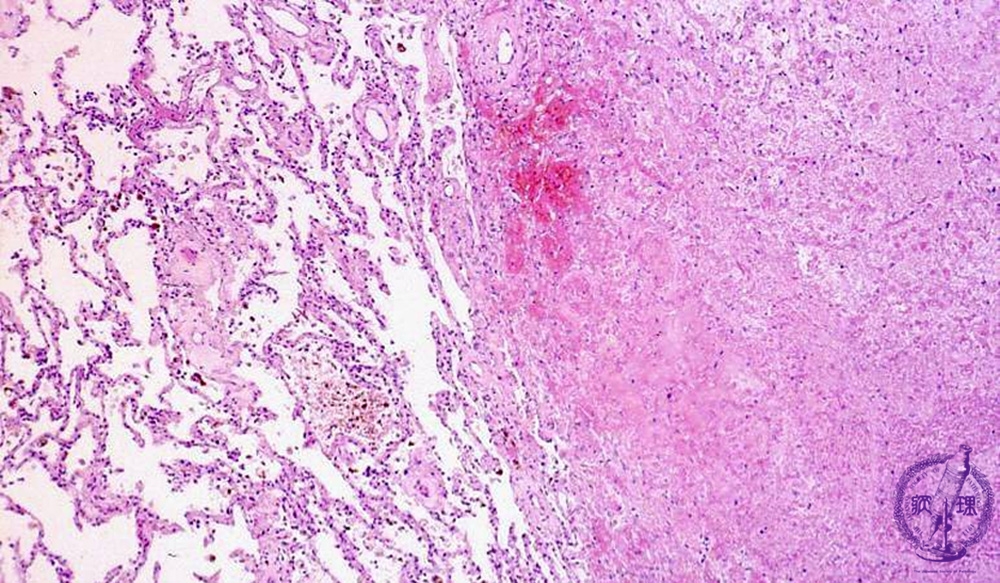

- (2)Hemorrhagic infarct of lung

Microscopic view (HE stain, low power view): On the right is an infarcted area associated with alveolar hemorrhage (arrow). Despite parenchymal cell necrosis, the outline of alveoli and nuclei remain faintly visible but nuclear staining is reduced (coagulative necrosis).